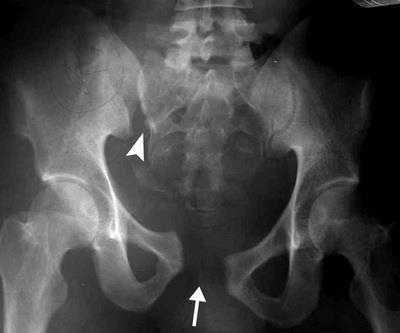

Рентгенография. Рентгенография обеспечивает возможность получения статических изображений плотных анатомических образований, например костей. Все переломы костей таза требуют рентгенологического исследования, нередко с использованием дополнительных проекций, которые позволяют врачу оценить характер смещения фрагментов.

Рентгенограмма нестабильного повреждения таза с разрывом лонного симфиза (стрелка) и крестцово-подвздошного сочленения (треугольная стрелка).